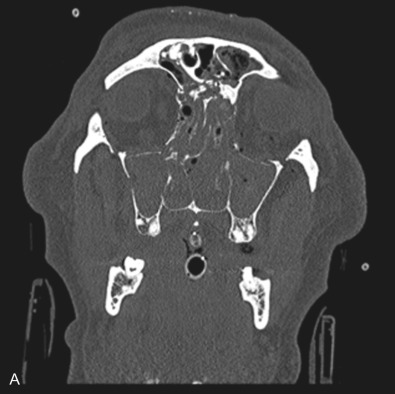

Le Fort I pattern fractures are characterized by a transverse fracture extending from the pyriform aperture, propagating laterally across the maxillary wall involving medial, anterior, and lateral components, and ending posteriorly at, or through, the level of the pterygoid plates ( Figs. 1.13.11–1.13.13 ). This results in mobilization of the lower third of the midface, whilst the upper two-thirds remains intact. The force is typically delivered above the maxillary teeth, causing a palatal/alveolar separation from the upper maxilla.